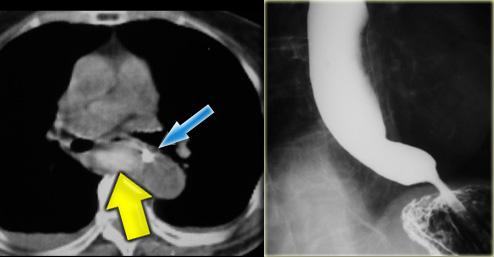

Bên trái là một trường hợp giả co thắt tâm vị khác.

Hẹp đoạn xa mô phỏng co thắt tâm vị, nhưng vị trí hẹp lệch tâm, các bờ vai không đối xứng (mũi tên), và niêm mạc không đều tại đỉnh vùng hẹp.

CT cho thấy thành đáy vị dày lên (mũi tên) do ung thư biểu mô tuyến.